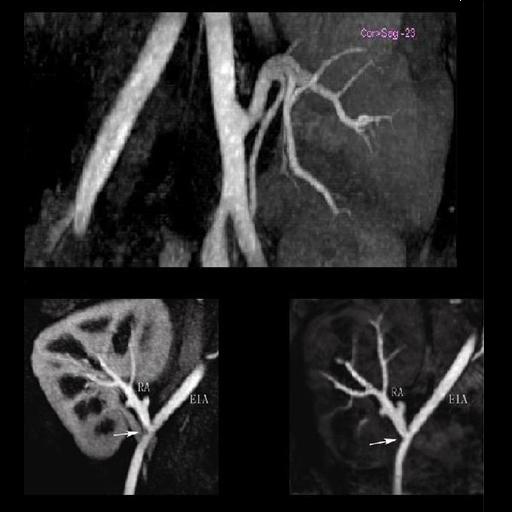

- NATIVE: Non-contrast MRA of ArTerIes and VEines – SPACE

and TrueFISP : Integrated software package with sequences

and protocols for non-contrast enhanced 3D MRA with high

spatial resolution. NATIVE particularly enables

imaging of abdominal and peripheral vessel NATIVE offers: • Non-contrast MRA • Separate imaging of arteries and veins • Visualization of – e.g. – renal arteries or peripheral

vessels The syngo NATIVE package comprises: • syngo NATIVE TrueFISP • syngo NATIVE SPACE

syngo NATIVE is a contrast-free MR angiography technique for

visualizing the vessels of the body. The package contains

protocols tailored for use in different body regions (e.g.

renal arteries, peripheral vessels). Inline Subtraction and

Inline Maximum Intensity Projection (MIP) further simplify

the workflow.

Clinical Applications

Alternative to contrast-enhanced MRA examinations when there

is contraindication to use of Gadolinium.

Additional Information

For non-contrast MR Angiography Siemens currently offers two

techniques under the category of syngo NATIVE — syngo NATIVE

TrueFISP and syngo NATIVE SPACE. syngo NATIVE TrueFISP is

based on the TrueFISP (True Fast Imaging with Steady state

Precession) sequence, which is a balanced steady state

gradient echo technique. The contrast mechanism for syngo

NATIVE TrueFISP comes from the preparation of the imaging

volume with a spatially selective inversion pulse, resulting

in the suppression of stationary tissue within the imaging

volume and suppression of signal from blood in the imaging

volume (e.g. venous blood). Blood which flows into the

imaging volume during the inversion time has the same

high-signal characteristics exhibited in that TrueFISP. The

contrast is further enhanced by the suppression of the

background by the inversion pulse. The sequence can be made

selective for arteries or veins by appropriate positioning

of the inversion pulse, which can be positioned

independently from the imaging volume. The sequence

accommodates 3D, 2D, breath-hold, syngo PACE (Prospective

Acquisition CorrEction) navigated and respiratory triggered

approaches depending on clinical environment.

The syngo NATIVE SPACE technique is a modified variable flip

angle 3D Turbo Spin Echo sequence in which the contrast

mechanism for visualizing vessels is based on the difference

in intravascular signal between maximal and minimal flow

during the cardiac cycle. The subtracted image is calculated

Inline and with Inline MIP generation, instantaneous

clinical results are produced for completely non-invasive MR

angiography, further improving workflow at the scanner. The

syngo NATIVE SPACE technique can also accommodate

multi-phase imaging that enables dynamic angiography — for

example, in the lower legs.

| Popliteal, anterior-posterior tibial and

peroneal arteries seen with syngo NATIVE |

VRT of the renal arteries with stenosis

generated from syngo NATIVE images |

Multi-step syngo NATIVE examination of the

pelvis and upper and lower legs vessels |

| Stenosis of the renal artery of the kidney

transplant (right: ceMRA) |

Visualization of the lower leg vessels with

syngo NATIVE |

Coeliac, superior mesenteric and renal arteries

seen with syngo NATIVE |